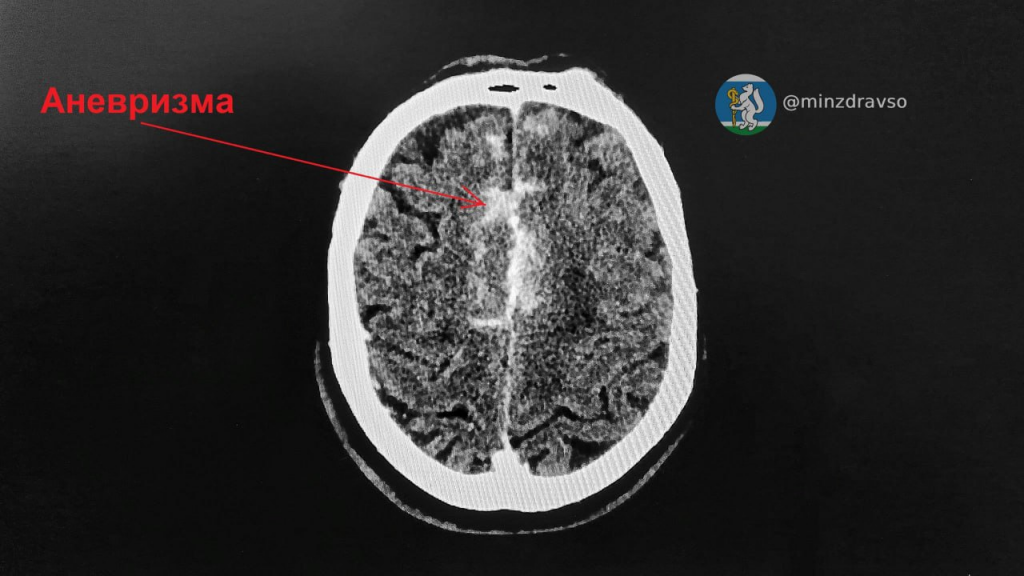

«Мужчина поступил в приёмное отделение без сознания, в коме. Специалисты немедленно провели сосудистую метаболическую терапию и КТ с контрастированием, выявили аневризму передней соединительной артерии и массивное субарахноидальное кровоизлияние. В этой ситуации единственный вариант спасения — срочная операция в Региональном сосудистом центре на базе Городской клинической больницы №40», — рассказала врач-невролог отделения неврологии ГКБ №14 Светлана Дёмина.